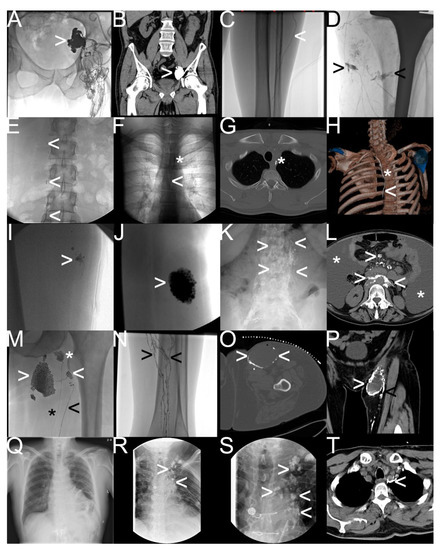

Figure 5.

Different types of iatrogenic lymphatic fistulas detected by “conventional lymphangiography“. Note: (A,B) after robot-assisted prostatectomy—iliac lymphocele (white arrowhead); (C,D) after total-knee arthroplasty—lymphatic feeder (white arrowhead) and percutaneous lymphatic fistulas (black arrowhead) leading to wound-healing disorder; (E–H) after radical thyroidectomy—mediastinal lymphatic fistula from the thoracic duct (white arrowhead) draining into the intraoperatively inserted drainage tube (white asterisk); (I,J) after soft tissue resection—typical lymphocele with blowout of oil-containing contrast material; (K,L) after chemotherapy for non-Hodgkin’s lymphoma—chylaskos (white asterisk), and chylothorax with pathological accumulation of the oil-containing contrast material in retroperitoneal and mesenteric lymph nodes; (M–P) postoperative lymphocele (white arrowhead) and lymphatic feeder (black arrowhead) with impaired lymphatic run-off in the calf (black arrowhead) in contrast to a healthy lymph node (white asterisk) and a healthy lymph duct (black asterisk); (Q–T) after cardiac surgery—refractory chylothorax and chylopericardium with multifocal pathologic extravasation and accumulation of oil-containing contrast material in the mediastinum (white arrowhead).